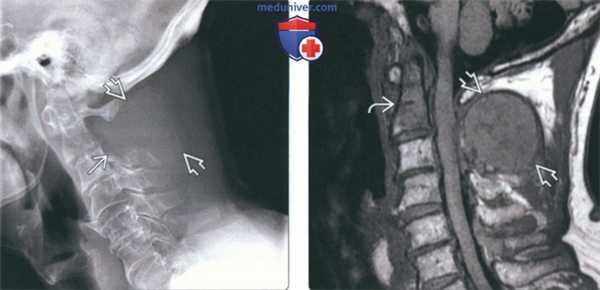

(Слева) На рентгенограмме в бо ковой проекции визуализируется мягкотканная опухоль, замещающая невральную дугу С2. Также определяется деструкция верхнего края боковых масс СЗ. Распространение деструктивных изменений от одной кости к другой нетипично для метастатического поражения.

(Справа) На сагиттальной MPT (Т1 ВИ) у этого же пациента визуализируется крупный очаг в невральной дуге С2. Костный мозг зубовидного отростка замещен опухолью. На рентгенограммах поражение зубовидного отростка выявлено не было - чувствительность МРТ в обнаружении метастазов выше.

2. Рентгенография при литических и бластических метастазах в шейные позвонки:

• Рентгенологические признаки:

о Для обнаружения литического очага он должен занимать 50-70% размера позвонка (> 1 см):

- Прямая проекция: отсутствие ножки

- Боковая проекция: деструкция кортикальной пластинки и/или замыкательной пластинки

о Склеротические очаги более заметны и обнаруживаются раньше

(Слева) На рентгенограмме в боковой проекции у пациентки с распространенным бласти -ческим метастатическим поражением на фоне рака молочной железы определяется диффузный склероз шейных позвонков и основания черепа. Видны наложения от сережек.

(Справа) На сагиттальной MPT (Т1 ВИ) определяются множественные остеобластические метастазы с сигналом крайне низкой интенсивности, свидетельствующим о их бластическом характере. Типоинтенсивный сигнал должен сохраняться и во всех стальных последовательностях.